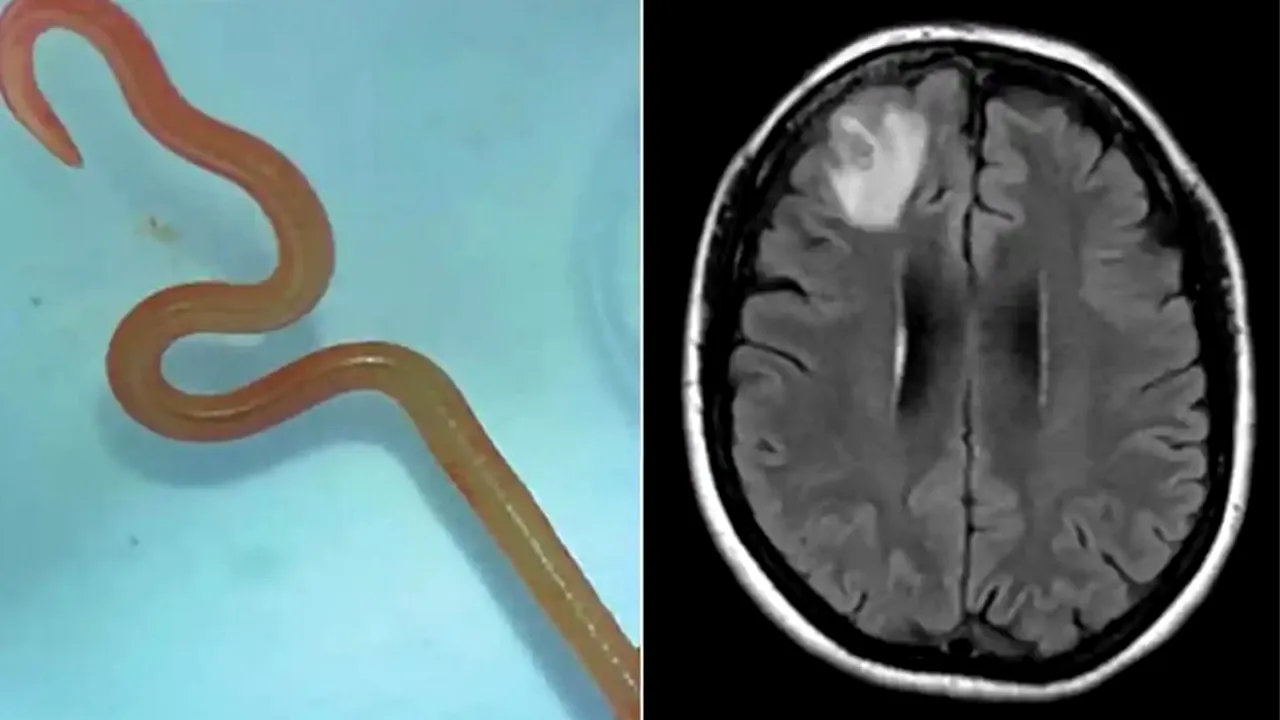

Un vierme care, de obicei, locuiește în pitoni, s-a aciuit în creierul unei femei. Parazitul viu, de 8 centimetri lungime, în acest caz, a fost găsit în cutia craniană a unei femei din Australia. “Ophidascaris robertsi”, pe numele lui, este un vierme rotund care locuiește de obicei în șerpii constrictori. Pacienta din spitalul din Canberra reprezintă primul caz din lume în care această creatură este descoperită în interiorul omului.

Până în 2022, simptomele ei au inclus și pierderi de memorie și depresie, ceea ce a dus la trimiterea ei la spitalul din Canberra. Un RMN la creier a dezvăluit anomalii care necesitau o intervenție chirurgicală.

„Neurochirurgii se confruntă în mod regulat cu infecții în creier, dar aceasta a fost o descoperire unică în carieră. Nimeni nu se aștepta să găsească așa ceva”, a declarat un medic, potrivit The Guardian.

„Canberra este un loc mic, așa că am trimis viermele, care era încă în viață, direct în laboratorul unui om de știință de la CSIRO care are multă experiență cu paraziții”, a spus medicul Sanjaya Senanayake. „S-a uitat la el și a spus: ‘Dumnezeule, acesta este Ophidascaris robertsi'”.Femeia locuiește în apropierea unei zone locuite de pitoni covor. În ciuda faptului că nu a avut contact direct cu șerpii, ea aduna deseori mirodenii din jurul lacului pentru gătit. Astfel, un piton ar fi putut răspândi parazitul prin intermediul fecalelor în iarbă, iar pacienta a fost probabil infectată cu parazitul direct prin atingerea ierbii sau după ce a mâncat verdețuri.